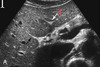

GB: Vesícula 1: Ligamento redondo

Vesícula contraída